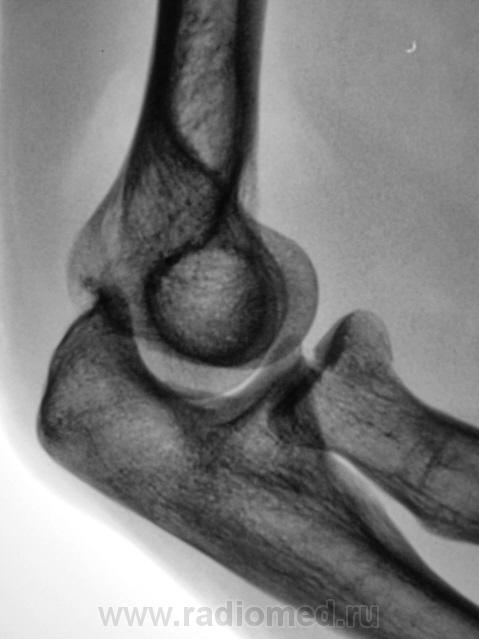

Фрагменты с увеличением.

Хочется услышать мнение коллег по поводу "жировых подушечек". Как они, среагировали или нет?

Вот два Ваших случая Валентин Львович в первом случае внутрисуставной перелом с гемартрозом ну и соответственная картина, а во втором случае гемартроза нет. Поправьте меня, если я шось неправильно рисанулsmiley

Следовательно, "отклонение" жировой ткани в виде образования "жировых подушечек", не свидетельствует, как утверждают многие, прямо, именно, о переломе, а свидетельствуют только о гемартрозе?